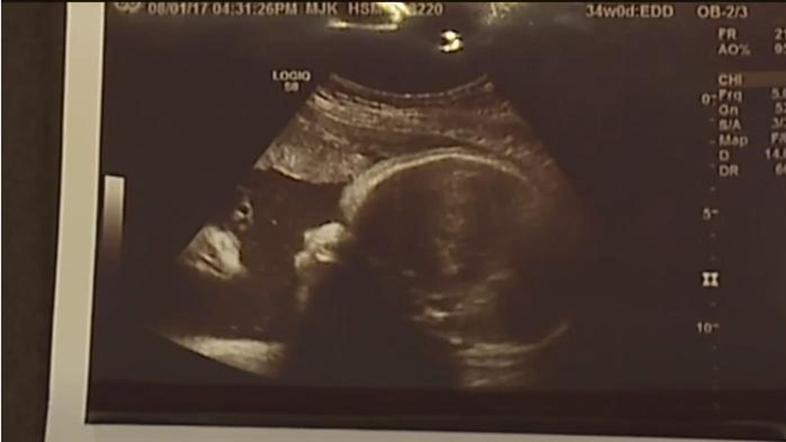

Starša šokirana, ko sta dobila slike dojenčice po ultrazvoku

Ko sta Alicia Zeek in Zac Smith videla fotografije z ultrazvoka svoje še nerojene hčerke, sta vedela, da je to Božji znak. Poleg obraza dojenčice je po njihovem mnenju še en obraz, starša pa trdita, da njunega otroka gleda Jezus. Svojo zgodbo in tudi fotografije ultrazvoka sta želela deliti z javnostjo.

"Ko so nama dali fotografijo, sem takoj vedela, da gre za Jezusa. Tudi videti je tako," pravi Alicia iz Chambersburga v ameriški zvezni državi Pennsylvaniji. Z njo se strinja tudi oče Zac.

Par trdi, da nista pretirano verna in dodajata, da jima je fotografija dala upanje, saj sta se prva dva njuna otroka rodila s prirojenimi napakami. Hči ima dva palca na eni roki, sin pa je imel razcepljeno ustnico in nebo. Fotografija ultrazvoka je dala paru upanje, da se bo njuna hči rodila brez kakršnih koli prirojenih napak in da bo zdrava. Tako se je tudi zgodilo, ko se je Briella rodila.